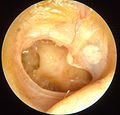

Chronic suppurative otitis media

Chronic suppurative otitis media involves a perforation (hole) in the eardrum and active bacterial infection within the middle ear space for several weeks or more. There may be enough pus that it drains to the outside of the ear (otorrhea), or the purulence may be minimal enough to only be seen on examination using a binocular microscope. This disease is much more common in persons with poor Eustachian tube function. Hearing impairment often accompanies this disease.